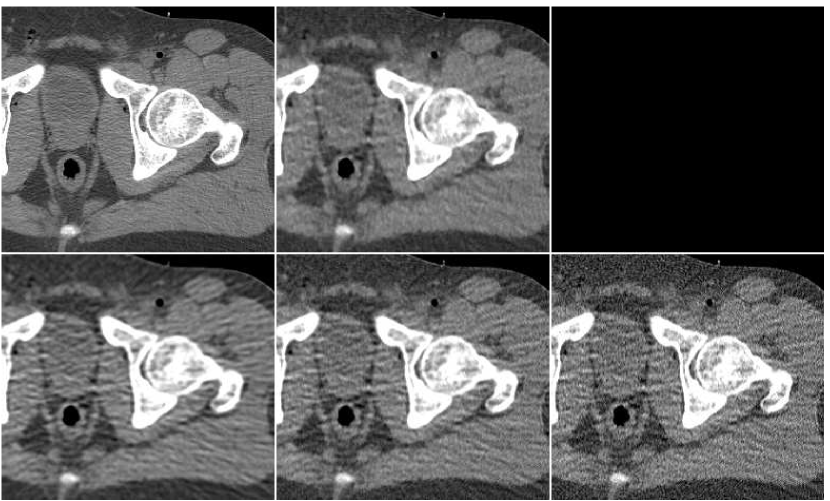

In Figure 10 we display the fusion result along with individual PWLS reconstructions, used in the fusion process. The lower part of the figure contains the absolute-valued error images. The fusion result has a higher visual quality than any of the three underlying images. Comparing to those images, the noise level in the fusion image is the lowest, and the tissue texture is closer to the original. The sharpness is the same as in the lower middle PWLS image. The SNR values (stated in the Figure) also point to the improvement in quality. The SSIM of the fusion image is , while the sequence of PWLS results have the SSIM values of (corresponding to the lower row of Figure 10, left to right). A reconstruction of an additional test image is displayed in Figure 11. The effect of the fusion observed here is similar to the one in the previous reconstruction. We conclude that the ANN-based fusion can contribute also to the iterative reconstruction, without requiring any additional iterations; the computational cost of the fusion, exercised after the reconstruction, is lower by an order of magnitude than that of the iterative process.

![]() |